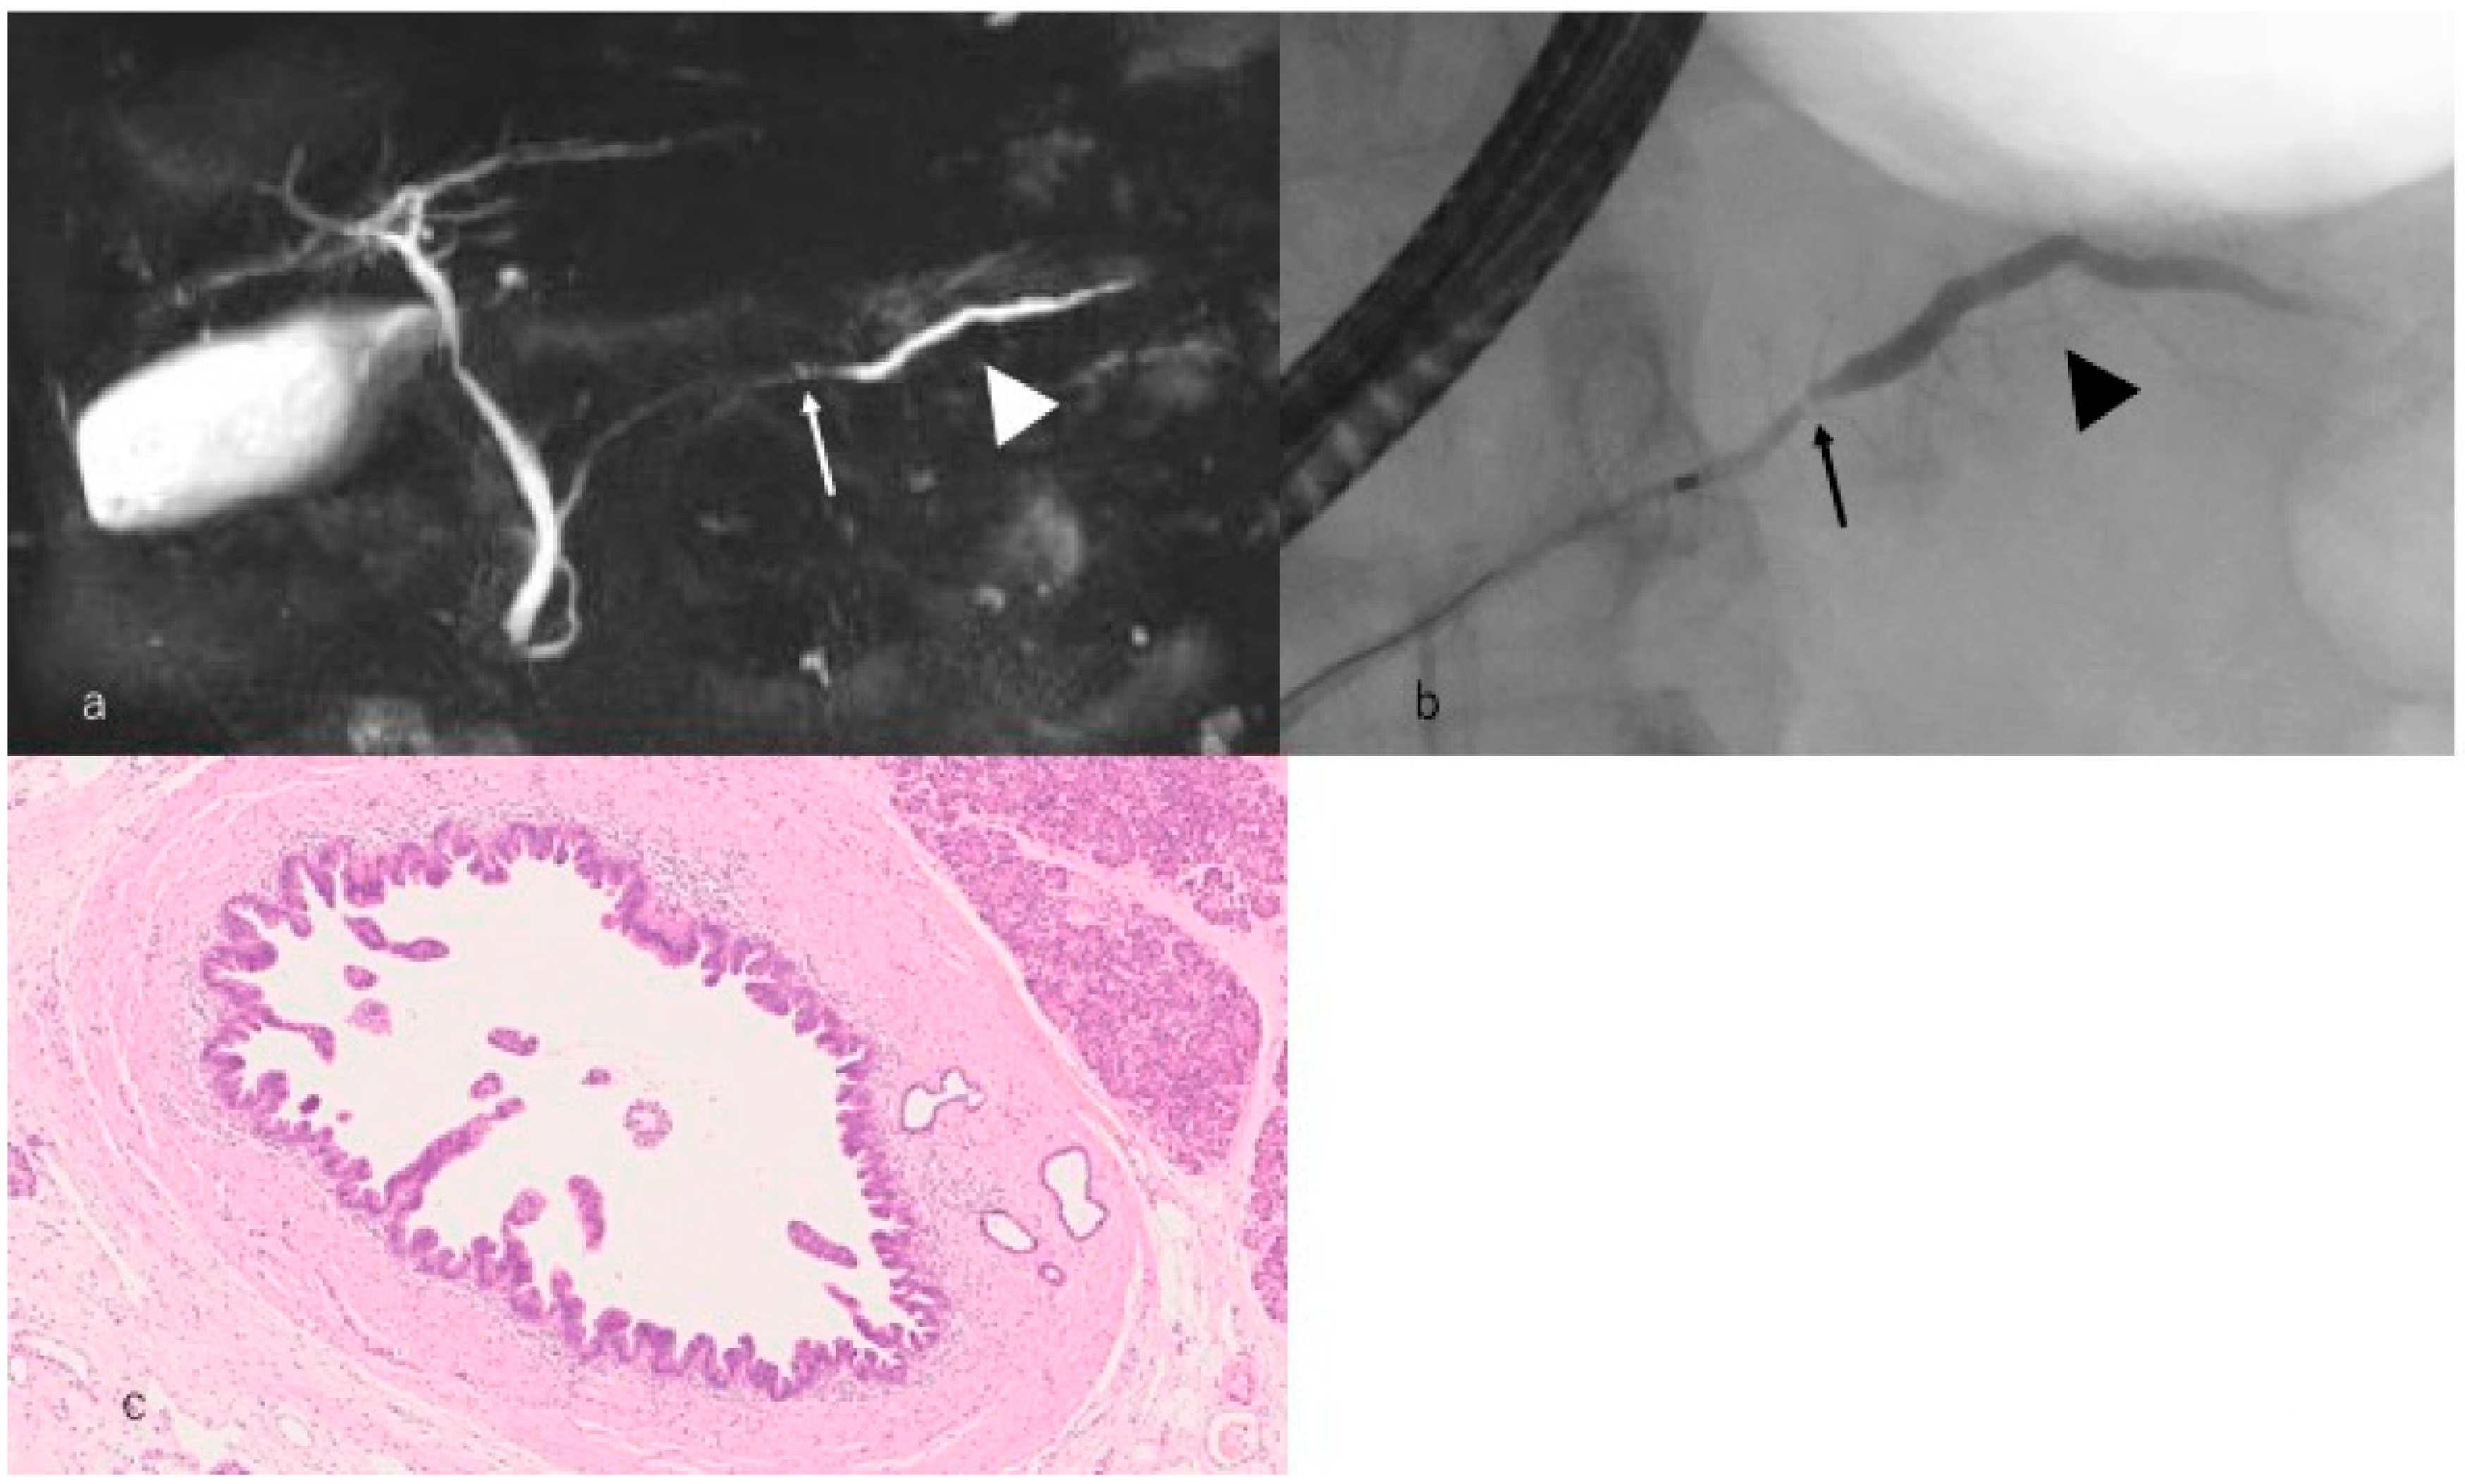

- Iiboshi, T.; Hanada, K.; Fukuda, T.; Yonehara, S.; Sasaki, T.; Chayama, K. Value of cytodiagnosis using endoscopic nasopancreatic drainage for early diagnosis of pancreatic cancer: Establishing a new method for the early detection of pancreatic carcinoma in situ. Pancreas 2012, 41, 523–529. [Google Scholar] [CrossRef] [PubMed]

- Hanada, K.; Okazaki, A.; Hirano, N.; Izumi, Y.; Teraoka, Y.; Ikemoto, J.; Kanemitsu, K.; Hino, F.; Fukuda, T.; Yonehara, S. Diagnostic strategies for early pancreatic cancer. J. Gastroenterol. 2015, 50, 147–154. [Google Scholar] [CrossRef] [PubMed]

- Hanada, K.; Okazaki, A.; Hirano, N.; Izumi, Y.; Minami, T.; Ikemoto, J.; Kanemitsu, K.; Hino, F. Effective screening for early diagnosis of pancreatic cancer. Best Pract. Res. Clin. Gastroenterol. 2015, 29, 929–939. [Google Scholar] [CrossRef] [PubMed]